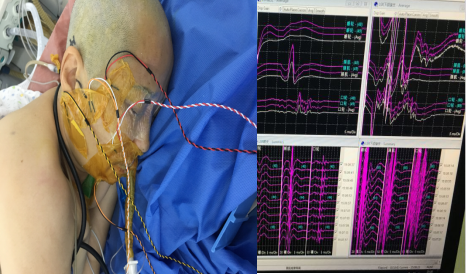

电生理监测下的右侧面神经微血管减压术

术中对面神经,三叉神经,副神经等重要神经进行实时电生理监测.